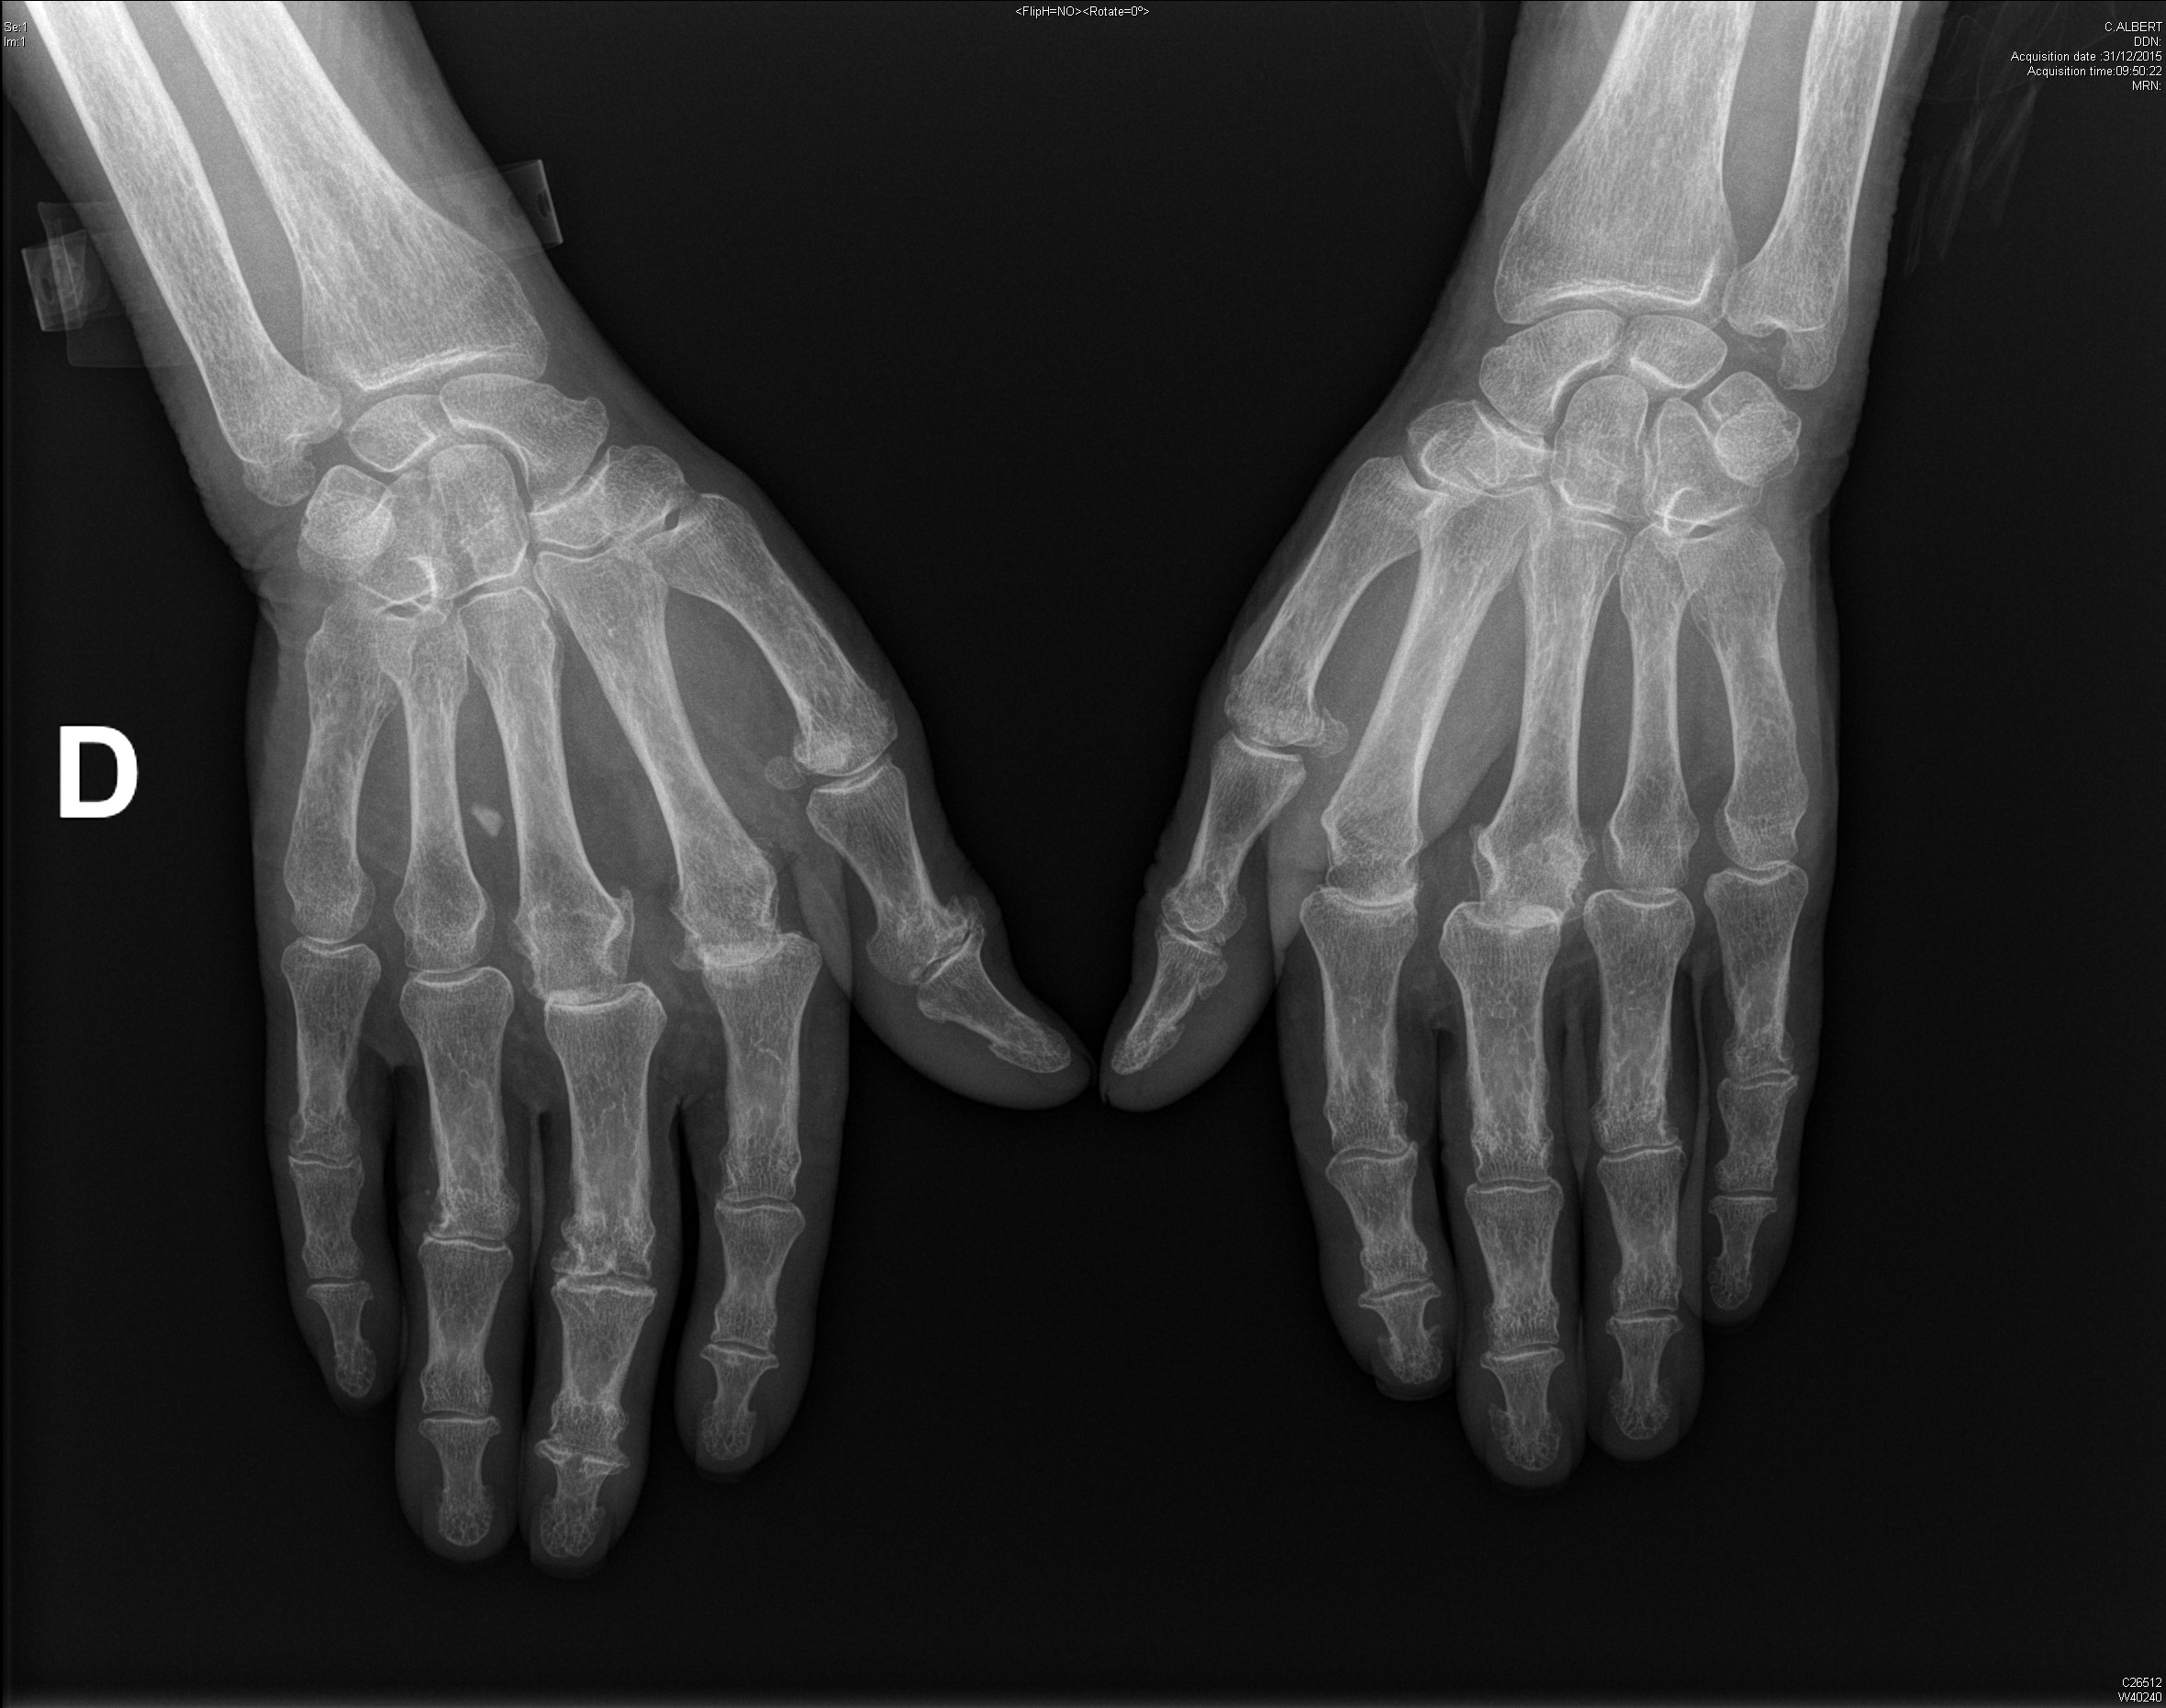

Polyarthrite rhumatoïde débutante, d'emblée érosive

polyarthrite rhumatoïde érosive avec signe de Freiberg radiographique au poignet